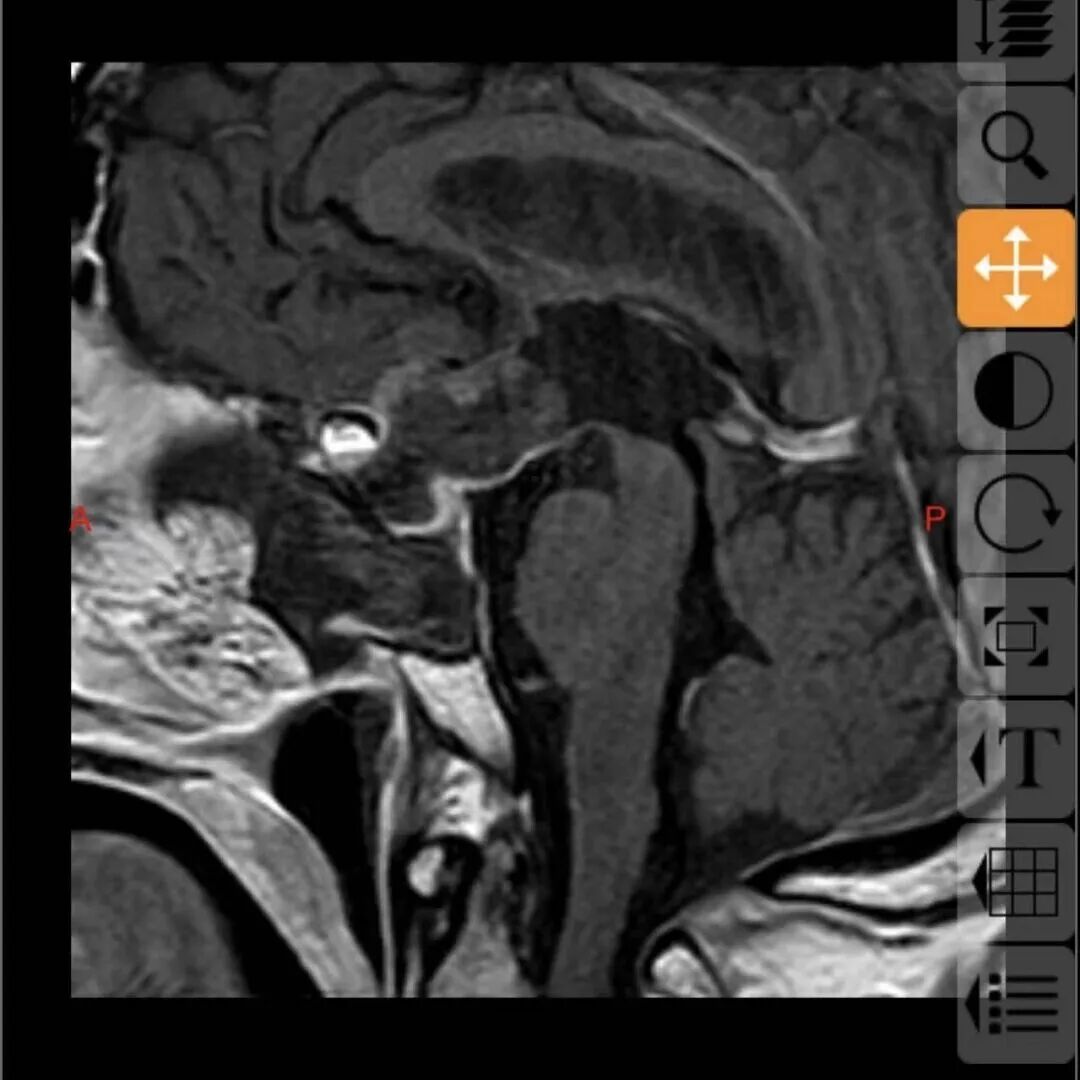

68岁的邓大叔是一位饱受垂体瘤困扰的“老战士”,11年前他经鼻行垂体瘤手术,几年后垂体瘤复发再次通过伽马刀治疗,经过两次历练后的他以为之后就可以高枕无忧,没想到近期的复查报告显示肿瘤“卷土重来”,且这次情况远比之前“棘手”,复发的肿瘤不仅从鞍内生长到鞍上,还与大脑的“生命线”——前交通动脉以及掌管意识记忆的三脑室底粘连紧密,甚至朝一侧颈内动脉上方生长,就像一颗埋在大脑深处的“不定时炸弹”,位置险要,结构复杂。

这颗复杂的“炸弹”究竟该如何拆除?张治国主任仔细研究了邓大叔的病情后,提出了一个大胆的方案:再次施行经鼻蝶微创手术。

最终,由张治国主任主刀,为邓大叔顺利实施了这例高难度的经鼻蝶微创手术,肿瘤被完整、精准地切除,紧密粘连的前交通动脉及三脑室底均保护完好。